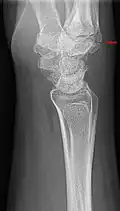

The joint between the index metacarpal and the capitate is a fibrous non-mobile joint. Some people have a gene that leads to this growth. It looks like arthritis (bone spurs on each side of the joint) on X-ray. It looks like a ganglion on the hand, but more towards the fingertips.

The carpometacarpal joint is usually found at the base of the second and third metacarpal bones at the point where they meet the small bones of the wrist.[2]